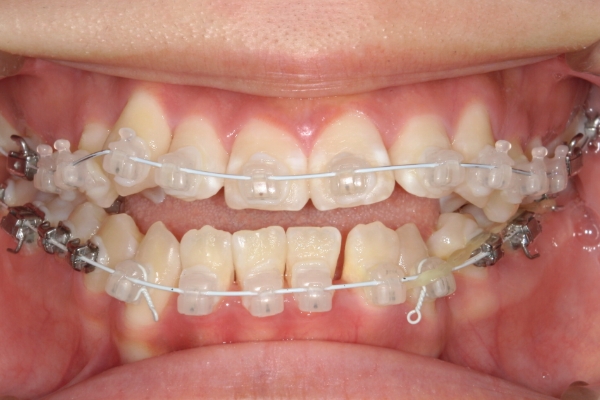

矯正治療

矯正装置を装着し、歯を動かし始めます。通院頻度は装置によって変わりますが、基本的には3~8週間に1回程度です。 1回の治療時間は20〜60分です。

1〜3か月毎にお口の中の写真を撮影し、患者さまへ治療の進行度をお伝えします。写真で歯並びの変化を実感していただくことは、患者さまご自身のモチベーションを保つことにもつながります。

PROCESS

3か月

骨格的に下あごが前下方に長いことが原因で、受け口、開咬(前歯が当たらない)の症状がでていました。また下あごが右にずれており、その影響で上下の歯列正中(真ん中)の大きなずれも生じていました。顎変形症手術も選択肢の一つでしたが、患者さまの希望もあり、下顎左側小臼歯の抜歯をして通常の歯列矯正で治療をしました。

前歯、奥歯の噛み合わせが大きく改善され、上下の歯真ん中が一致しました。食べ物が噛みやすくなったこともですが、歯列の見た目が整った点にも患者さまは満足されていました。